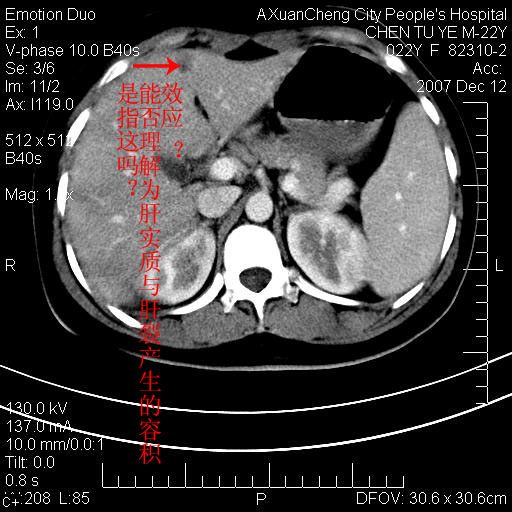

各位战友看看病灶在什么地方,可是右前叶进肝裂部低密度影,平扫ct值约10以下,增强后增高明显

平扫与增强ct值差>10hu的话,应该列为高度疑似病例,我们的职责就是不能放过这样小的病灶.再次b超对比

确定是否同一病灶!运到伪影我坚决反对!

不均匀脂肪浸润,版主所说的病灶为肝园韧带服着点。

考虑肝圆韧带。